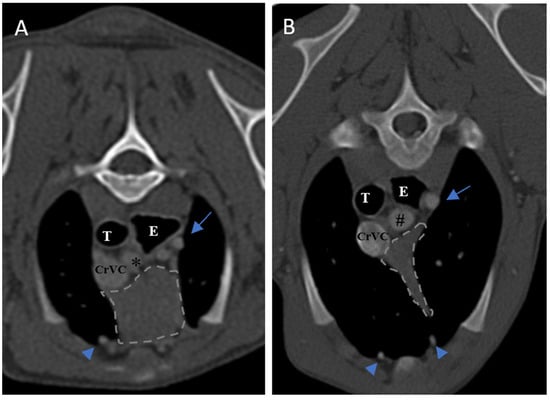

The size of the thymus was also measured in transverse and dorsal images. The maximum height (TH) and diameter (TD) in transverse images and maximum diameter (DD) and length (DL) in the dorsal views were measured (Figure 2), as well as thymic volume (TV) in all groups. These indices were measured in the area related to the mediastinal fat at the normal location of the thymus for patients with a completely fatty replacement of the thymus (grade 0). All measurements were performed in contrast-enhanced examinations. To normalize the thickness of the thymus in the transverse view, the height of the second thoracic vertebra midbody was measured and the ratio was calculated. The correlation between thymic size and grade with the body fat content was evaluated by measuring the thickness of subcutaneous fat in the dorsal aspect of the T4 spinous process (Figure 3). Subjective characteristics such as predominant deviation of the thymus to left, midline or right position, the thymic shape (wedge shaped, rectangular shaped, or linear shaped), and the thymic contour (convex and concave) were also evaluated. For patients with fatty degeneration, these characteristics were analyzed in mediastinal fat at the location of the previous thymus. Evaluation of thymic size, volume, attenuation, and grade was performed twice by a single person within a week, and the mean value of the first and second measurements for numerical data and the second results for thymic grading were reported.

Figure 3. Demonstration of measurement of subcutaneous fat content at the level of T4 in a transverse section of post-contrast CT examination.